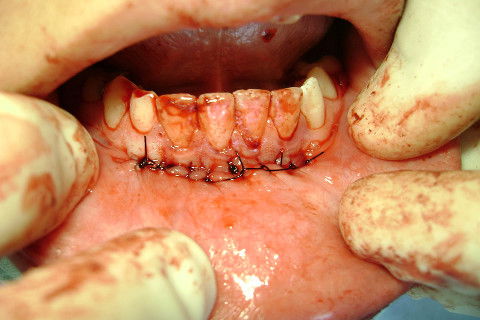

Sutura interrompida simples.

Resolvi fazer uma sutura continua festonada entre os espaços da sutura simples.